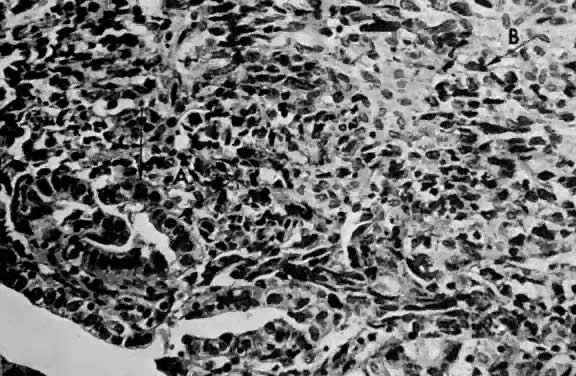

The homologous variety contains sarcomatous elements derived from tissue normally present in the uterus. These tumors are commonly referred to as carcinosarcomas (Fig. 14 and Fig. 15).

Fig. 14. Mixed homologous mesodermal sarcoma showing islands of adenocarcinoma ( A) scattered in a leiomyosarcomatous stroma ( B) (H&E, × 350)

Fig. 15. Mixed homologous mesodermal sarcoma composed of islands of adenocarcinoma ( A) and squamous carcinoma ( B) with leiomyosarcoma ( C) (H&E, × 350)

The heterologous variety contains sarcomatous elements derived from tissue foreign to the uterus. These tumors are commonly referred to as mixed mesodermal tumors. The name should include the term heterologous because this is specific (Fig. 16, Fig. 17, and Fig. 18).